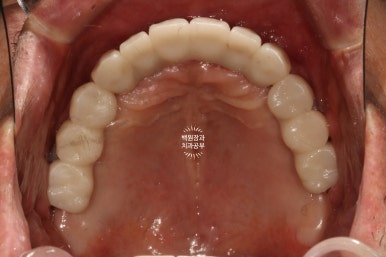

씹는면에서 본 임시치아입니다.

이제 제법 치아의 모양을 갖췄네요. 여기까지 오는데 7개월이라는 시간이 걸렸습니다.

그리하여 완성된 최종보철물입니다!!

옛날부터 임플란트 틀니용으로 사용하시던 임플란트 3개는 임플란트 주위염이 조금 있어 약~간 쇠기둥 색깔이 보인다는 단점이 있긴 하지만, 다른 임플란트들은 꽤나 예쁘게 제작이 되었네요.

위 아래 교합면 사진을 보시면, 과연 이게 임플란트인가? 싶으실거에요. 치아에 지르코니아 크라운을 붙인 것과 큰 차이를 못느낄 정도로 정말 자기 치아같이 예쁘게 제작된 임플란트 크라운을 보실 수 있습니다!!